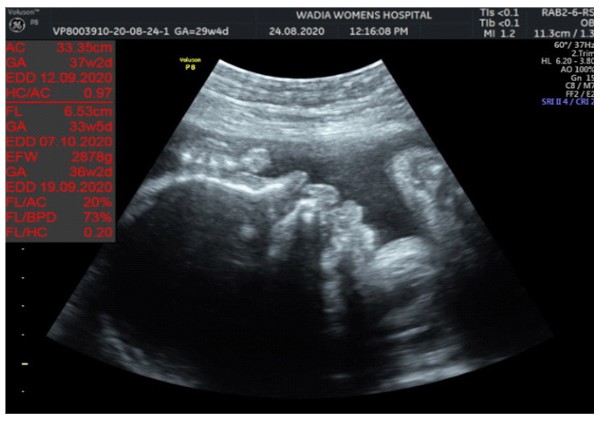

In the third conception during the COVID-19 pandemic, the couple presented to us in the third trimester. Anomaly screening ultrasound at 18 weeks done elsewhere was unremarkable, but subsequent scan done at our institute at 29 weeks was suggestive of fetal biometry corresponding to 26 weeks, head circumference below 1st centile, composite growth along 3rd centile. The fetus had microcephaly and sloping forehead; head circumference measured 241 mm (less than 1st centile for gestational age) (Figure 1). Transcerebellar diameter measured 23.6 mm (<1st centile) with vermis spared suggestive of cerebellar hypoplasia (Figure 2). The Cavum Septum Pellucidum (CSP) was enlarged measuring 22 mm x 10 mm (Figure 3). Additional ultrasound findings were corpus callosum agenesis, kinked thalami, widened subdural spaces and right club foot (Figure 4). The ultrasound differentials were pontocerebellar hypoplasia or Walker Warburg syndrome.